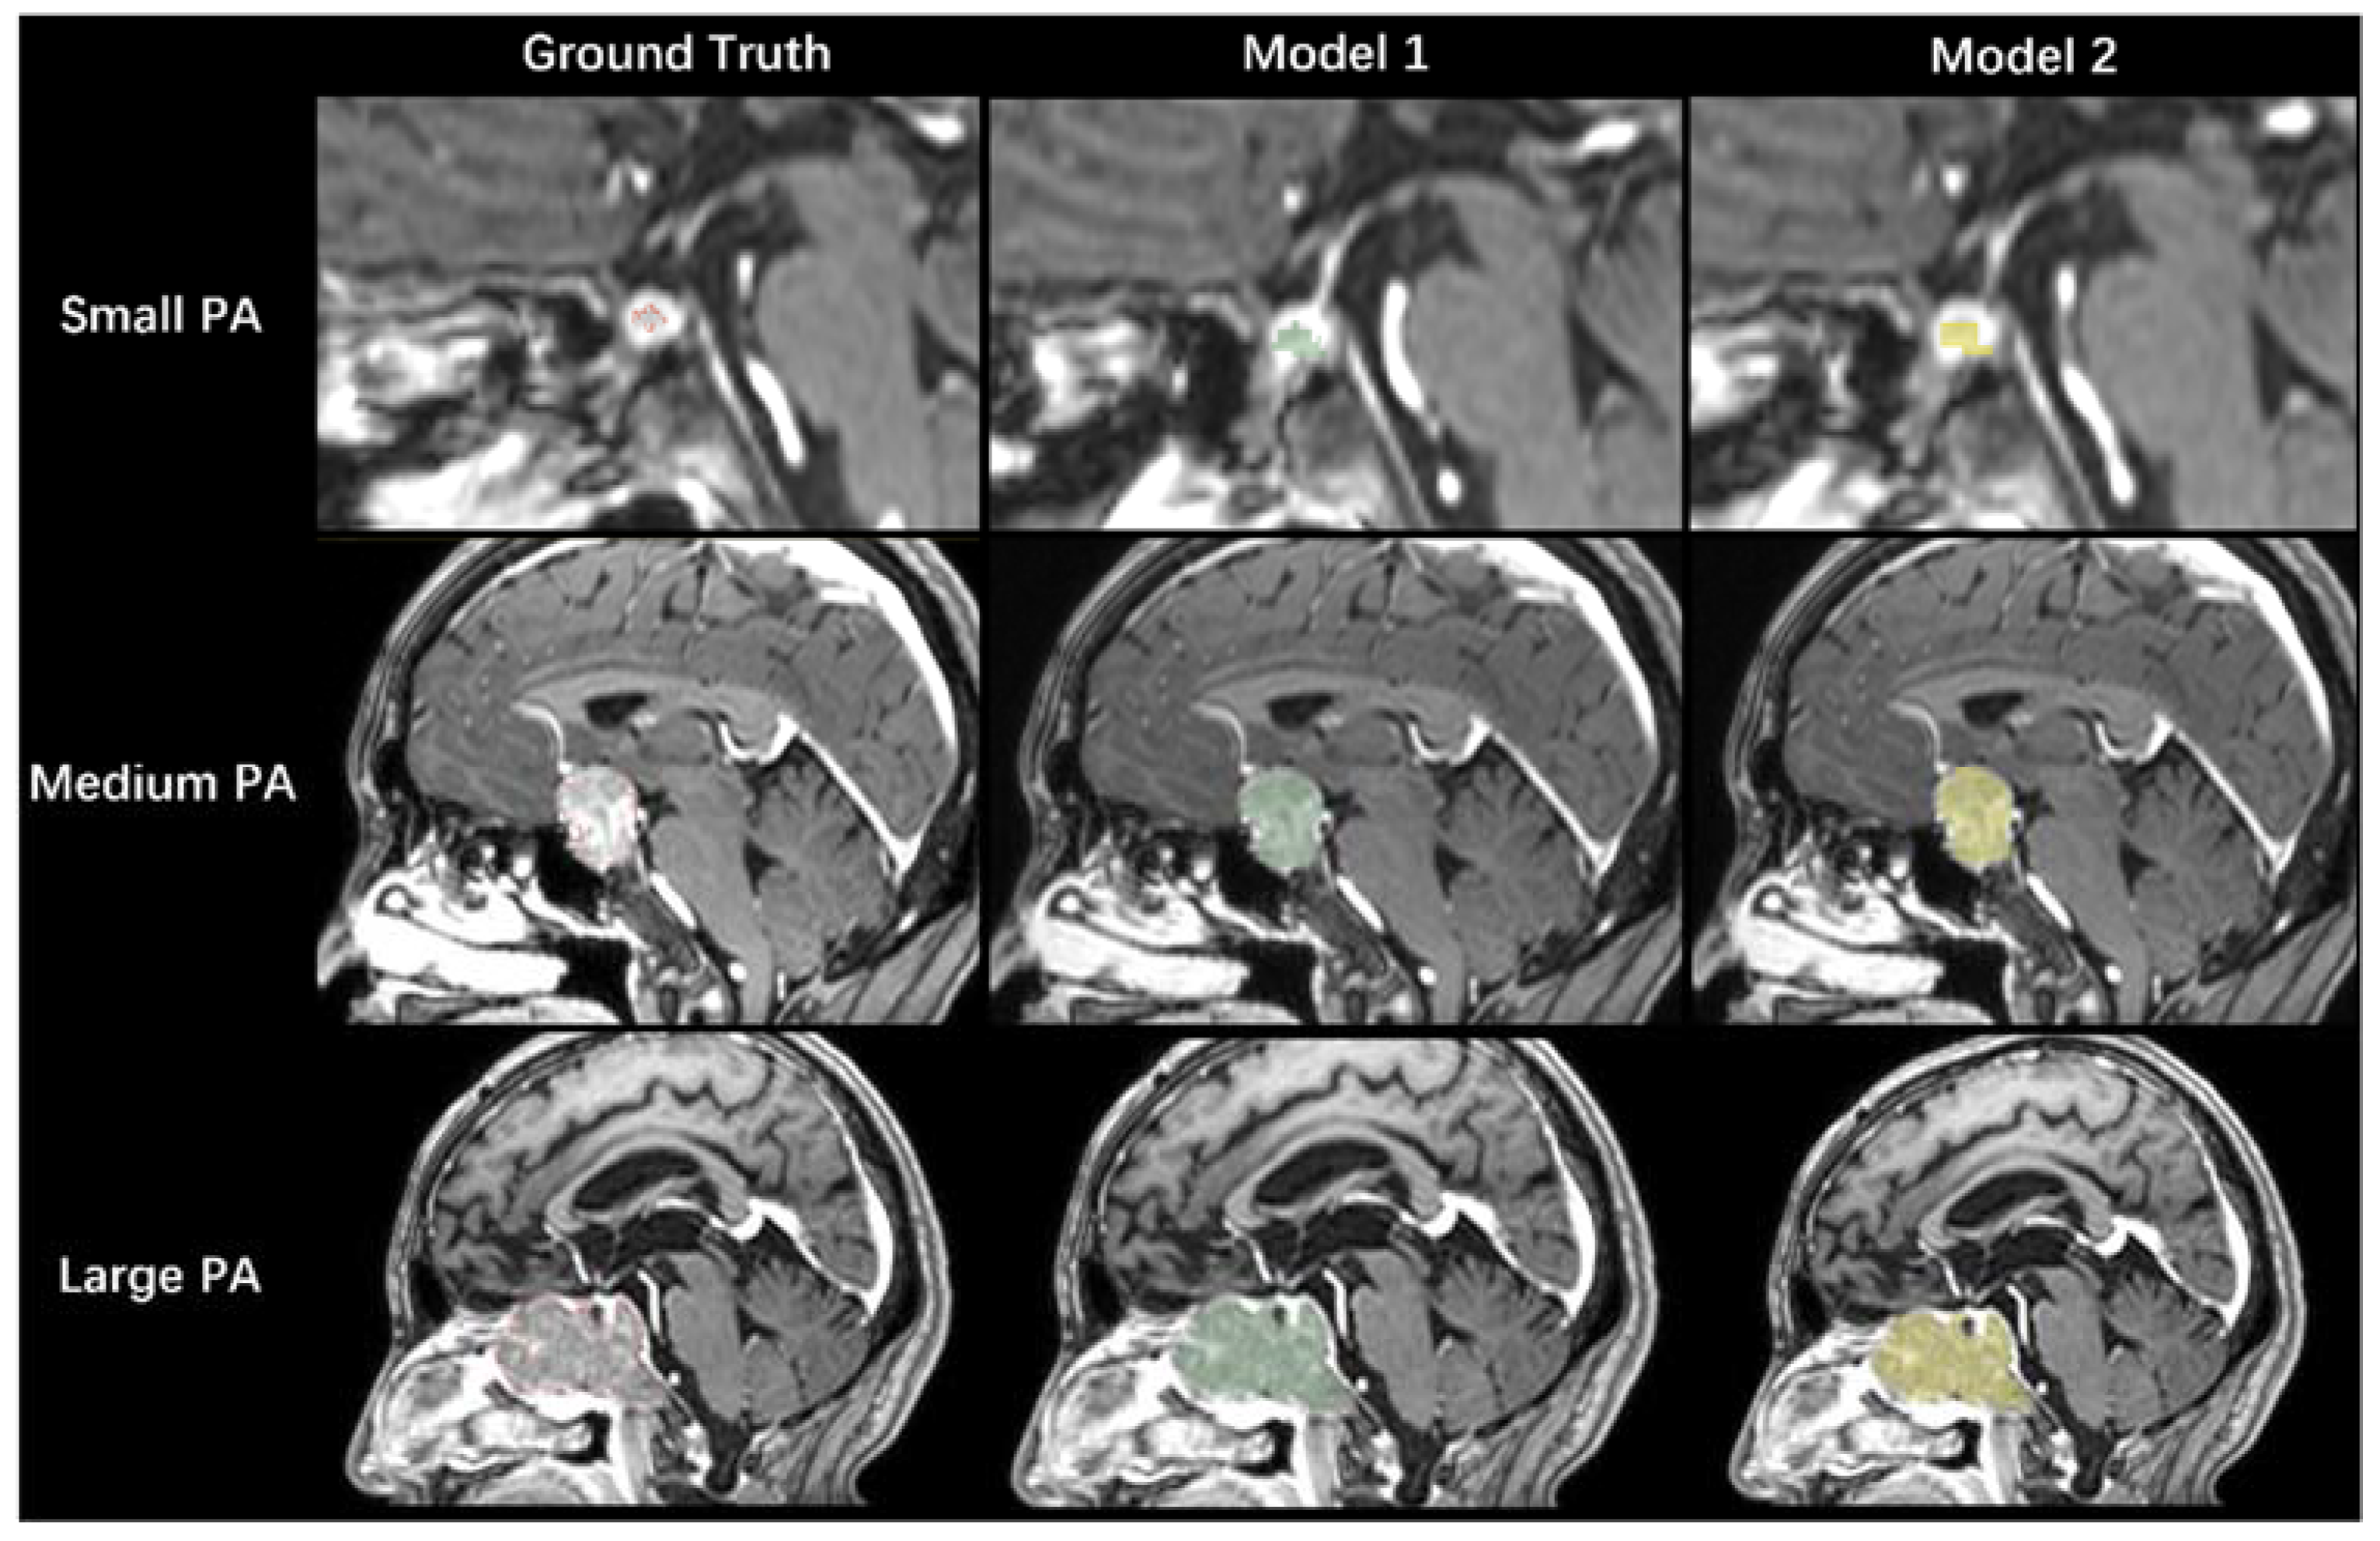

3.4. Model Performance in the Testing Dataset

3.5. Performance Comparison between the Two Models

3.6. The Relationship between DSC Values and PA Volumes